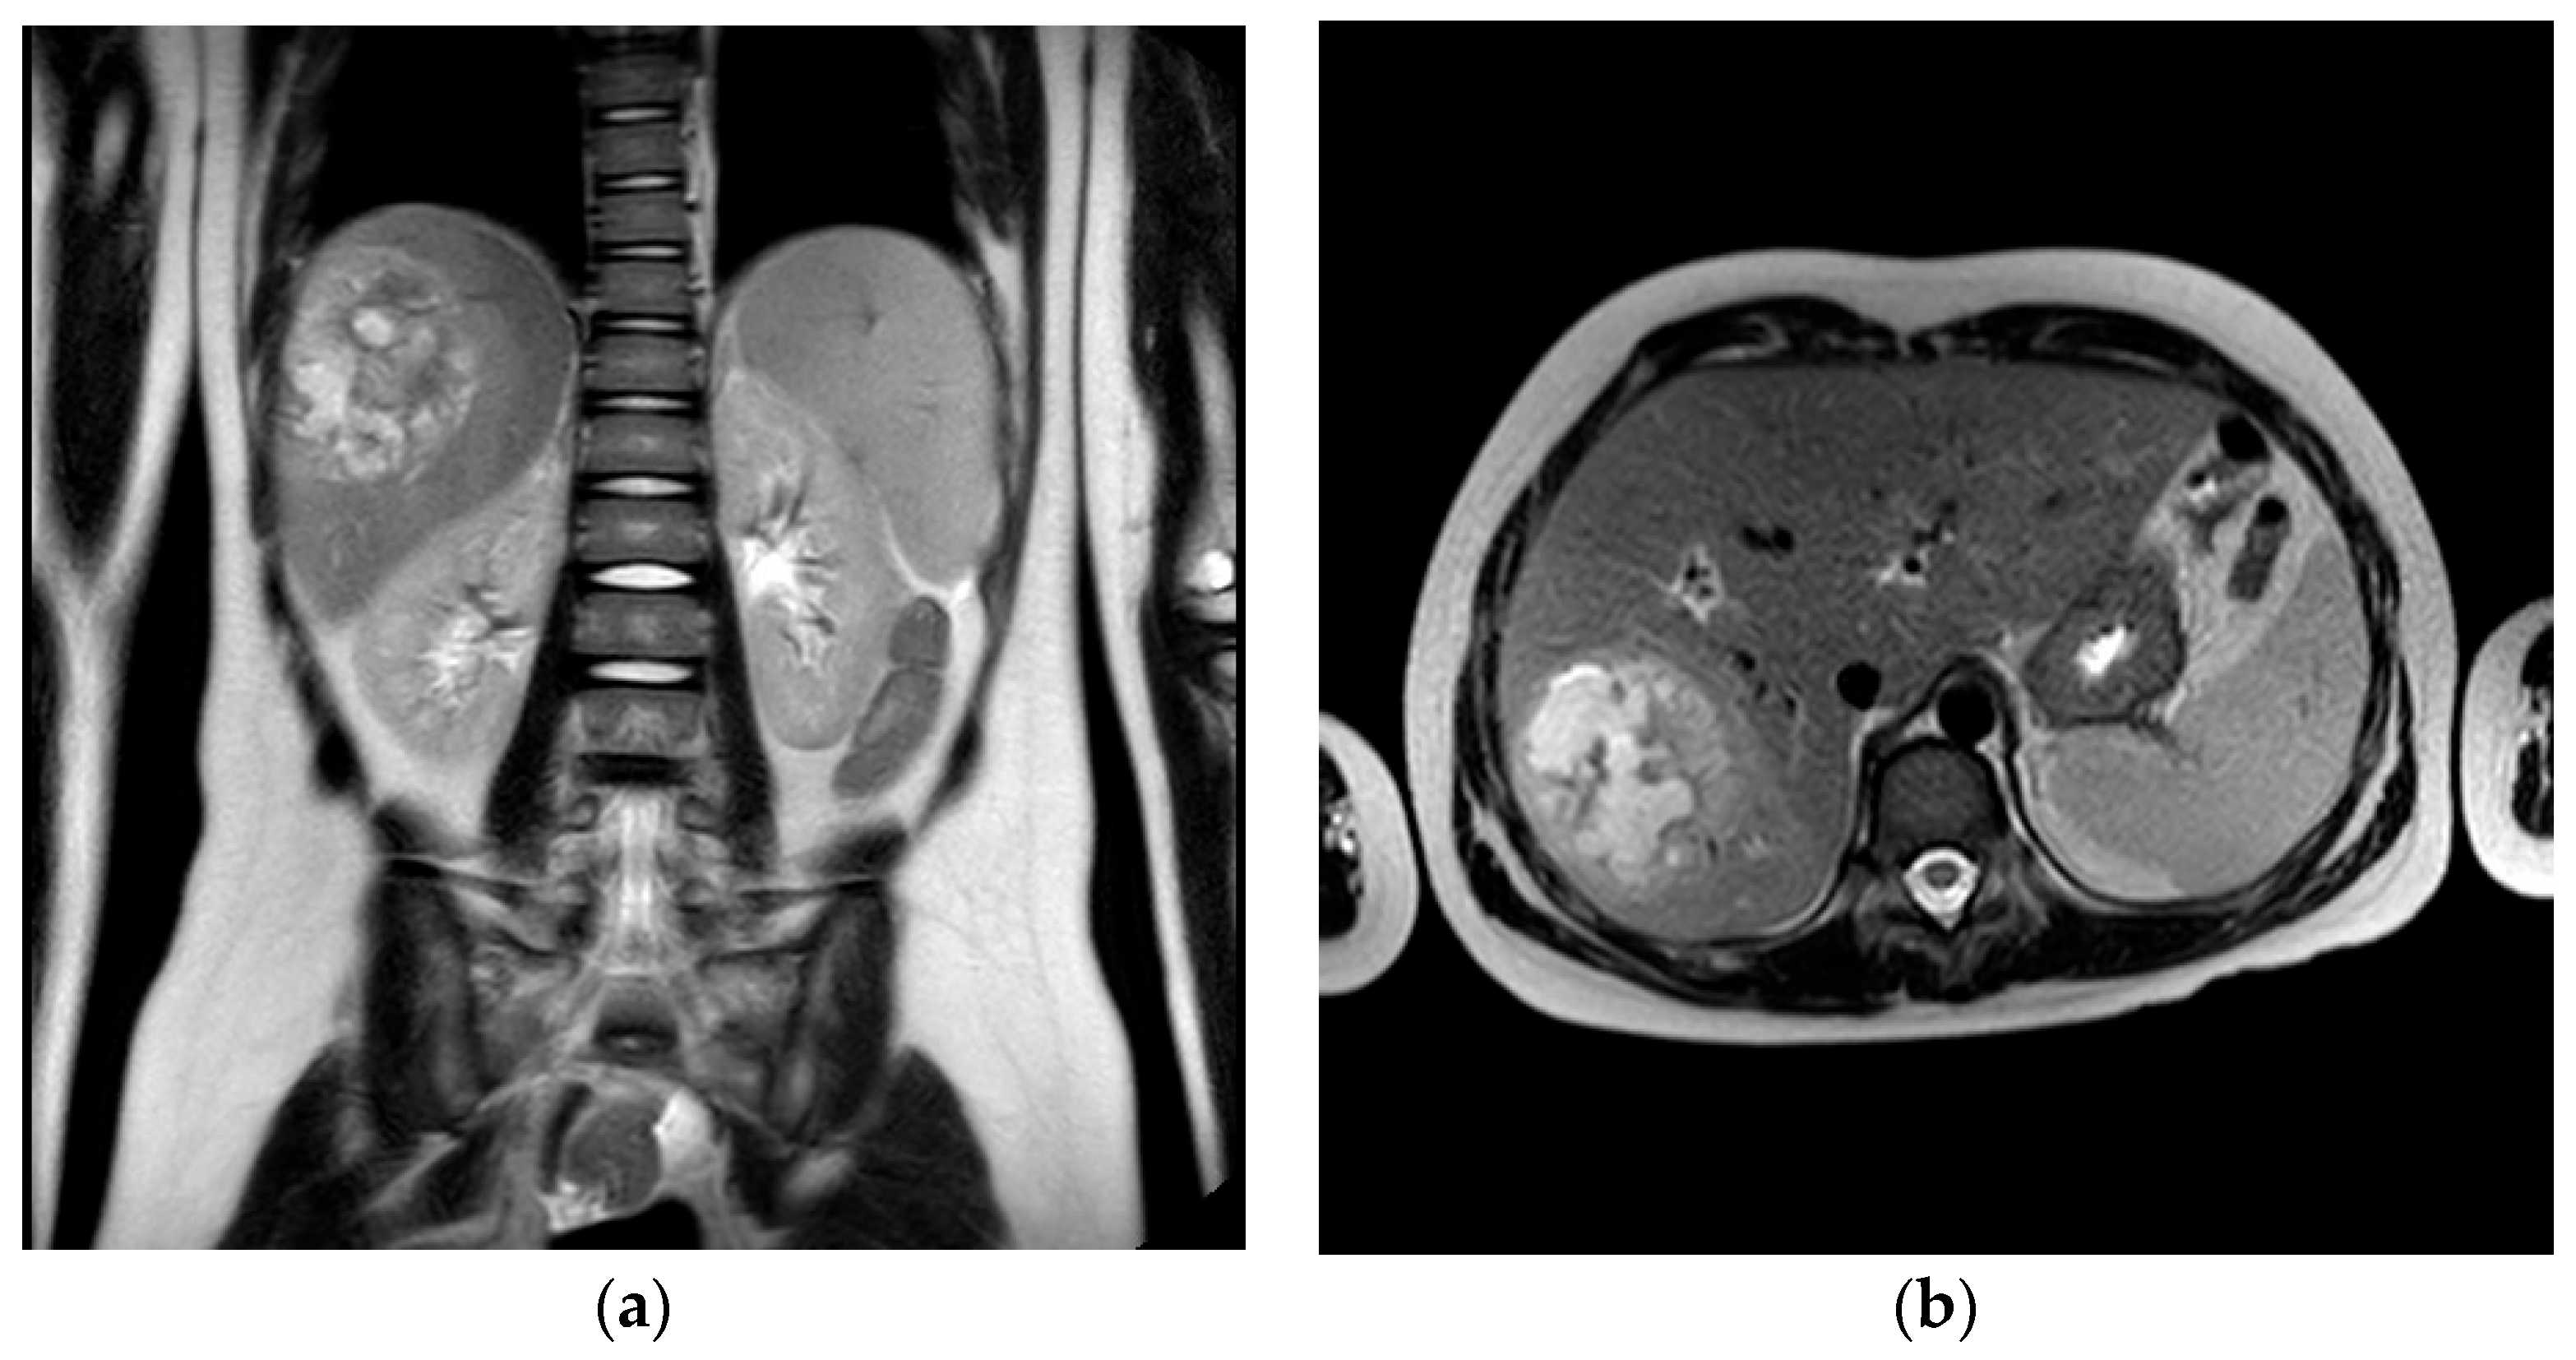

2.1.2. Initial Assessment and Hematological and Radiological Investigations

2.1.3. Microbiology Investigations